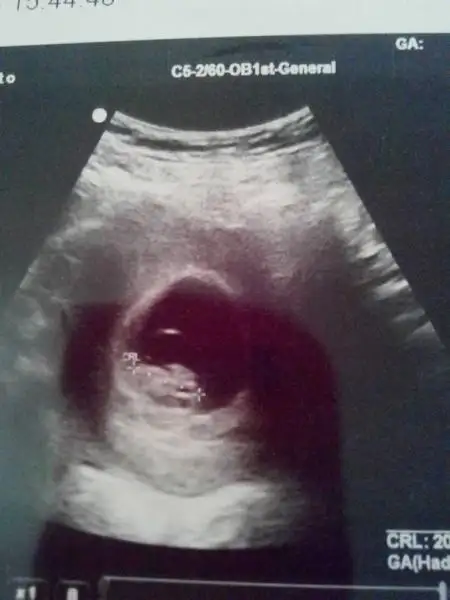

Bu da bizim 8+1 5 gün önden gidiyor. Oglumda fasulye gibi kesesi bunda yuvarlak...

sizin kese tam fasulye şeklinde yani erkek ama sağa yatkın o zaman kız:) benim kese yuvarlak kız diyorlar ama bebek sola yatkın o zman da erkek çıkıyo var bu işte bi terslik